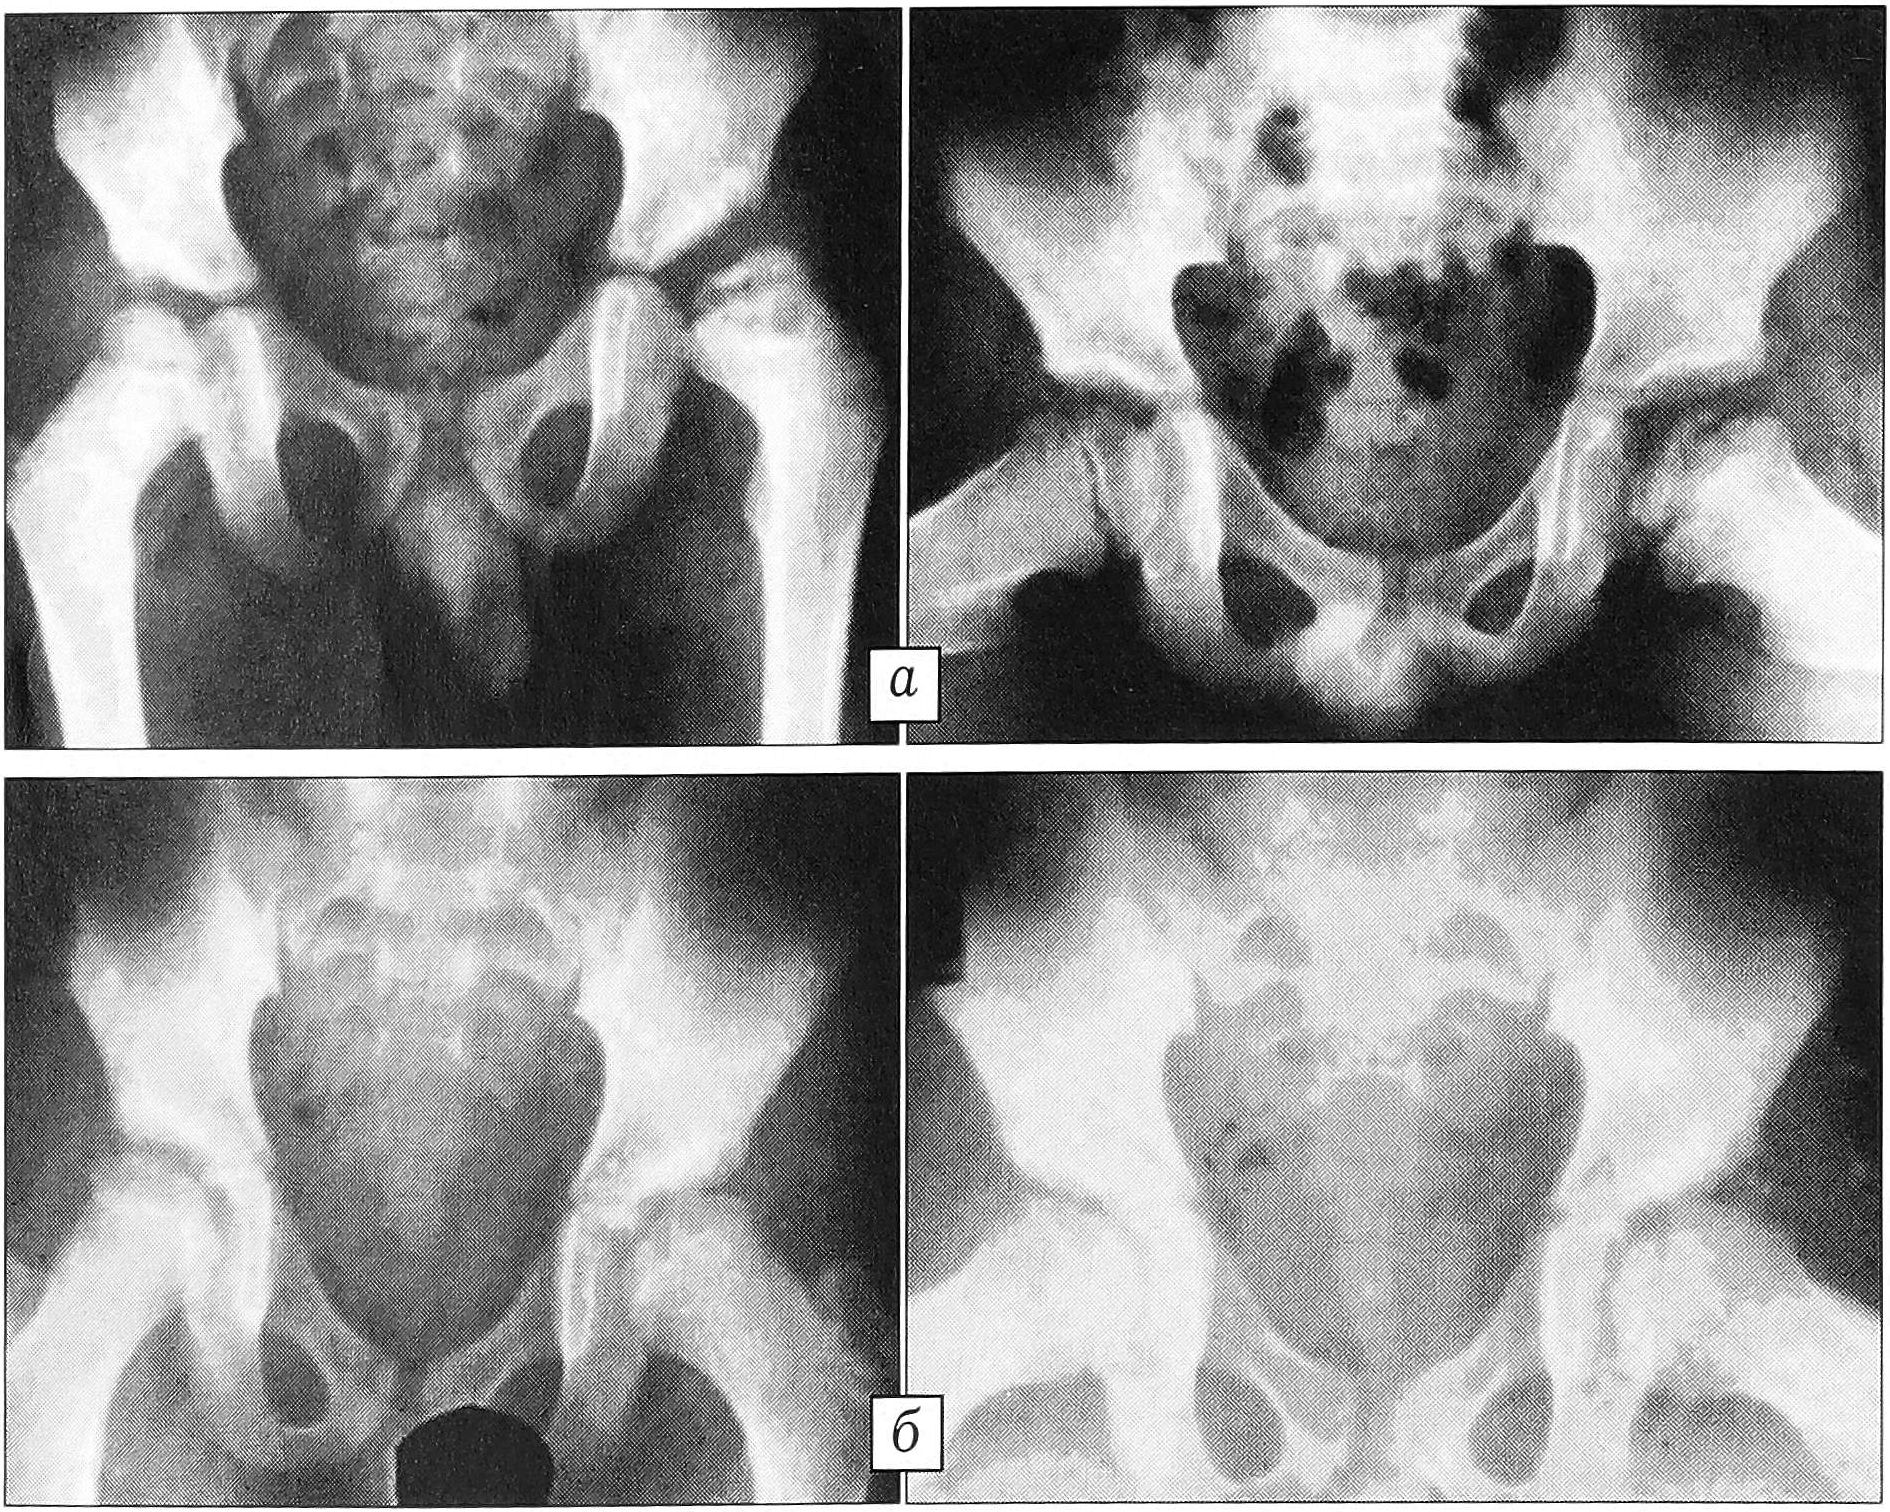

При хирургической коррекции варусной деформации шейки бедра (coxa vara) мы применяли терапевтически активную соломку АРЕКОС с целью создания благоприятных условий для развития микроциркуляторной сети, стимуляции костной регенерации. Как указывалось выше, в состав этого материала входят оротовая кислота и глюконат кальция. Выделяясь в окружающие ткани путем диффузии, они способствуют нормализации белкового обмена в диспластических тканях шейки бедра и создают антимикробную среду. Оперированы 24 ребенка с coxa vara (33 сустава) в возрасте от 3 до 16 лет. Выполнялась корригирующая межвертельная остеотомия с устранением всех компонентов деформации. Фиксация осуществлялась Г-образной металлической пластиной, при этом проводилась трехканальная туннелизация шейки бедра через патологический очаг до ростковой зоны с введением активной соломки. Гнойно-воспалительных осложнений не наблюдалось. На 23 оперированных бедрах уже к 4-му месяцу после операции отмечены консолидация костных фрагментов и закрытие зоны псевдоартроза, в остальных 10 случаях это произошло в обычные сроки (6—7 мес). У 19 детей результат расценен как хороший, у 5 (7 суставов) как удовлетворительный, плохих исходов не было.

Клинический пример. Больная Л., 5 лет. Диагноз: варусная деформация шейки левого бедра (рис. 3, а, б). Поступила с жалобами на хромоту. До обращения в ЦИТО получала консервативное лечение — без эффекта. 17.10.89 выполнены корригирующая межвертельная остеотомия левого бедра с фиксацией пластиной, туннелизация шейки и введение биосоломки АРЕКОС (рис. 3, в). В дальнейшем проводилось функциональное лечение без гипсовой иммобилизации. Через 3 нед пациентка выписана на амбулаторное лечение. К 4 мес наступила консолидация костных фрагментов в положении коррекции, сократилась зона патологической перестройки, достигнут полный объем движений в тазобедренном суставе (рис. 3, г). Пластина удалена через 6 мес после операции. При осмотре через 1 год: девочка не хромает, объем движений в тазобедренных суставах полный, на рентгенограмме зона патологической перестройки не определяется (рис. 3, д, е) .

Рис. 3. Больная Л. 5 лет. Диагноз: «дистрофическая» варусная деформация шейки левого бедра. а — внешний вид больной, б — рентгенограмма до операции; в — рентгенограмма после корригирующей остеотомии левого бедра с фиксацией пластиной «ДОН» и туннелизацией шейки биосоломкой АРЕКОС; г — рентгенограмма через 4 мес после операции; д — рентгенограмма, е — клинический результат через 1 год после оперативного лечения.